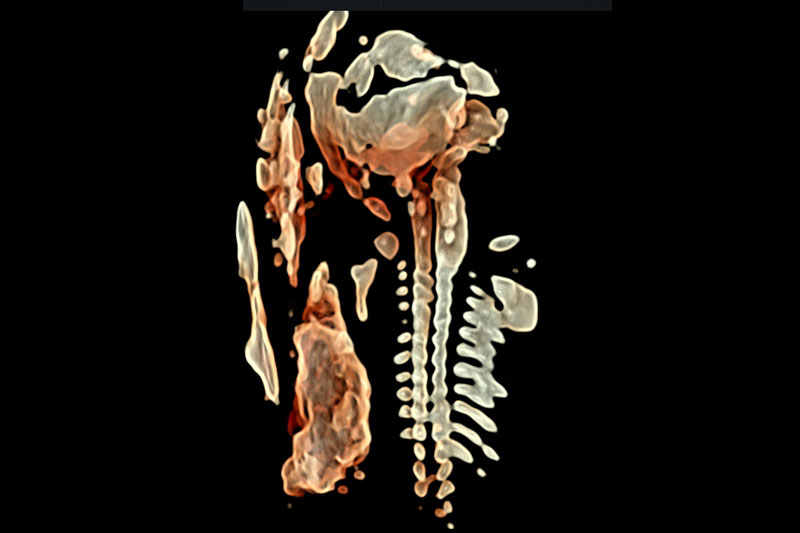

FMF-certified scanning protocols, high-resolution ultrasound, and global screening standards.